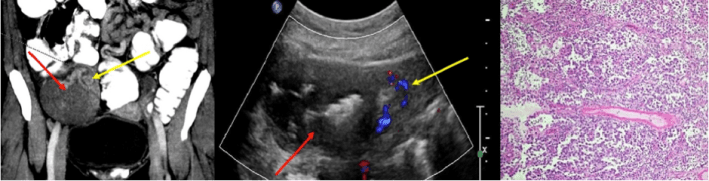

Poster abstracts – FPM Centenary Conference – 7th December 2018

14c

940 × 240 pixels